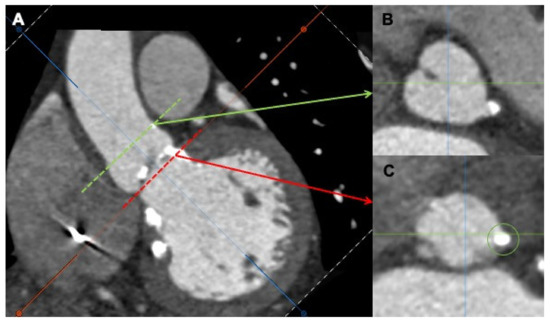

Paravalvular Leakages after Surgical Aortic-Valve Replacement and after Transcatheter Aortic-Valve Implantation: Strategies to Increase the Success Rate of Percutaneous Closure

Moderate to severe paravalvular-leak (PVL) regurgitation after surgical aortic-valve replacement or after transcatheter valve implantation represents a well-known complication associated with symptoms related to heart failure, hemolysis, or both in patients with multiple comorbidities and with poor prognostic outcomes. The transcatheter closure of [...] Read more.

Moderate to severe paravalvular-leak (PVL) regurgitation after surgical aortic-valve replacement or after transcatheter valve implantation represents a well-known complication associated with symptoms related to heart failure, hemolysis, or both in patients with multiple comorbidities and with poor prognostic outcomes. The transcatheter closure of aortic paravalvular leaks (APVLs) is currently considered a valid alternative to cardiac surgery. Nevertheless, careful patient selection, optimal cardiac imaging for intraprocedural guidance, and expert operators are key for success. Although technically demanding, particularly in APVLs after transcatheter valve implantation, catheter-based closure is an effective, less invasive, and often the only option for high-risk patients with symptomatic PVL regurgitation. Full article

Show Figures

Figure 1